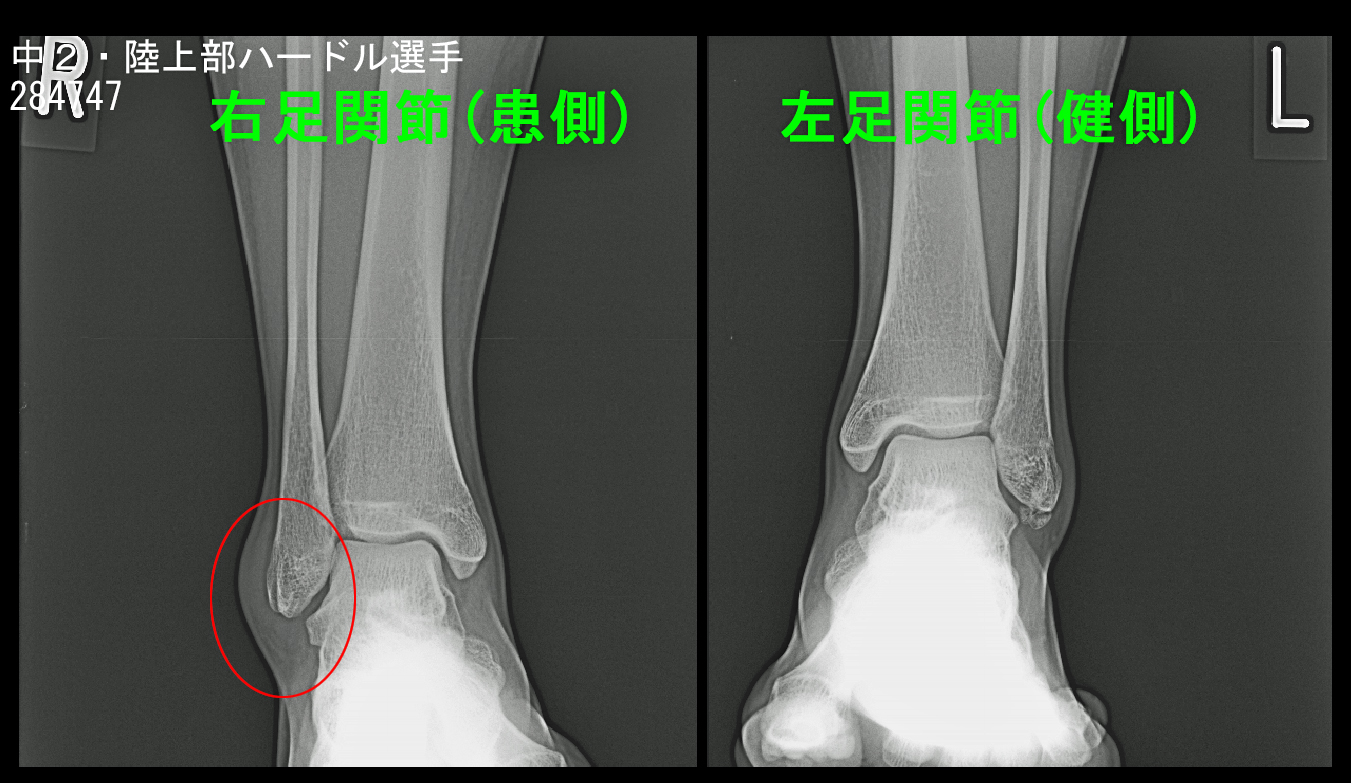

次は14才中学2年の陸上部のハードルの女子選手です。平成26年9月6日のリレーの練習で右足関節を捻挫し、かろうじて歩行ができる状態で当日受診されました。1週間後の9月13日に新人戦の県北大会があり、ハードルとリレーに出場予定だそうです。

14才女 Xp1.jpg

右足関節の外側は左足関節に比して腫れています。普通なら出場は無理と判断されるでしょう。私はMRI検査を行い、骨に損傷がなければ、左足関節の注射の治療で出場できるかもしれないと説明しました。

14才女 MR1.jpg

MRI検査(骨が黒く見えるSTIRという条件)では患側の右足関節には骨の損傷はなく、関節部の白さが広がっており(赤矢印)、関節内に出血を認める関節炎の所見です。健側の左足関節の距骨の後ろ側が軽度高輝度を示しており、こちらはケガしていないのですから、元々の運動による痛みを伴っていない疲労骨折の前駆状態と理解されます。このようなことはしばしば見られるものです。